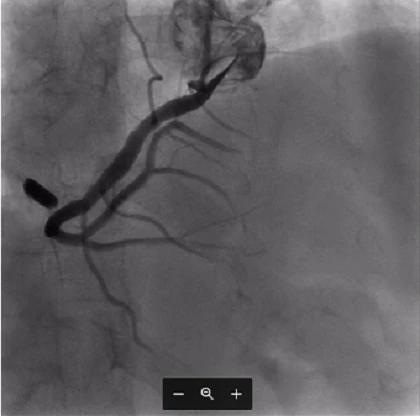

Qua siêu âm, bác sĩ ghi nhận người bệnh bị hở van ba lá rất nặng, tim phải giãn lớn. Bên cạnh đó, khi xem phim X-quang ngực thẳng và chụp mạch vành, các bác sĩ phát hiện trong tim có một mảnh dị vật cản quang.

Các bác sĩ quyết định chụp MSCT không cản quang cho người bệnh để xác định vị trí của dị vật. Bàn bạc cùng gia đình và người bệnh, TS-BS Nguyễn Hoàng Định, Trưởng khoa Phẫu thuật tim mạch - BV ĐH Y Dược, quyết định vẫn sẽ phẫu thuật.

Ảnh chụp X-quang dị vật.